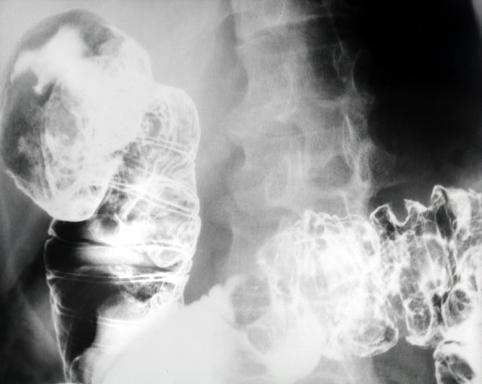

A case of malignant lymphoma which mainly involved the small intestine with multiple polypoid lesions.

Malignant Lymphoma/Malignant lymphoma

Duodenum/More than one of above

X-ray

25 - 29